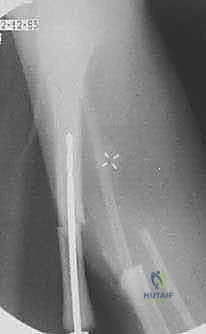

الخطوات الجراحية التفصيلية لعملية تثبيت قصبة الساق بقضيب ويليامز

تحت قيادة الأستاذ الدكتور محمد هطيف، يتم إجراء هذه الجراحة وفق بروتوكول عالمي صارم يضمن أعلى نسب النجاح. الجراحة ليست مجرد "تثبيت كسر"، بل هي إعادة بناء شاملة للطرف.

الخطوة الأولى: التقييم والتحضير والتخدير

تتم دراسة صور الأشعة السينية والرنين المغناطيسي بدقة لرسم خريطة ثلاثية الأبعاد للتشوه. يتم تخدير الطفل تخديراً عاماً، مع مراقبة حثيثة للوظائف الحيوية. يتم استخدام جهاز الأشعة المرئية (C-arm Fluoroscopy) داخل غرفة العمليات لتوجيه الجراح في كل خطوة.

الخطوة الخامسة: إدخال قضيب ويليامز

يتم اختيار قضيب ويليامز بالطول والسمك المناسبين بناءً على قياسات دقيقة. يتم إدخال القضيب من أعلى قصبة الساق (قرب الركبة) أو من أسفلها، ليخترق القناة النخاعية، ويعبر منطقة الكسر، ليصل إلى الجزء الآخر من العظم، مما يضمن استقامة الساق وتثبيت الكسر بقوة.